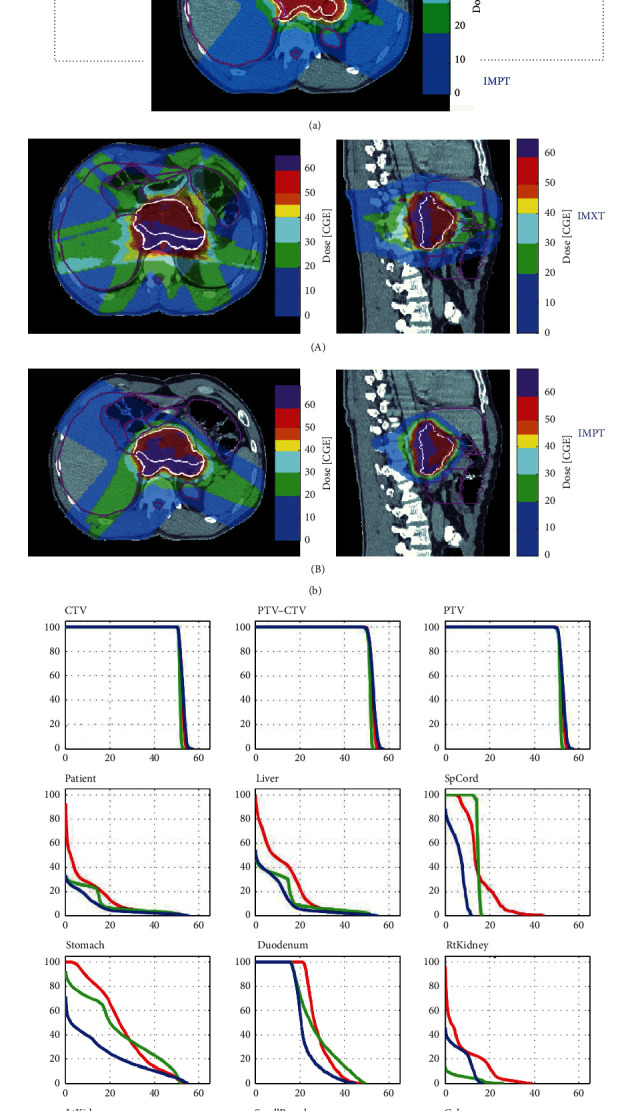

Results: CTVs ranged from 74 to 357 cc (mean 188 cc). Dose conformity was improved with IMPT, while 3D CPT provided better dose homogeneity. Mean dose to the liver, small bowel, and stomach was reduced with IMPT compared with 3D CPT or IMXT.

Conclusions: IMPT, 3D CPT, and IMXT provide excellent target coverage for retroperitoneal sarcomas. OAR dose is lower with IMPT and 3D CPT, and IMPT achieves the closest conformity. These techniques offer the opportunity for further dose escalation to areas with positive margins.